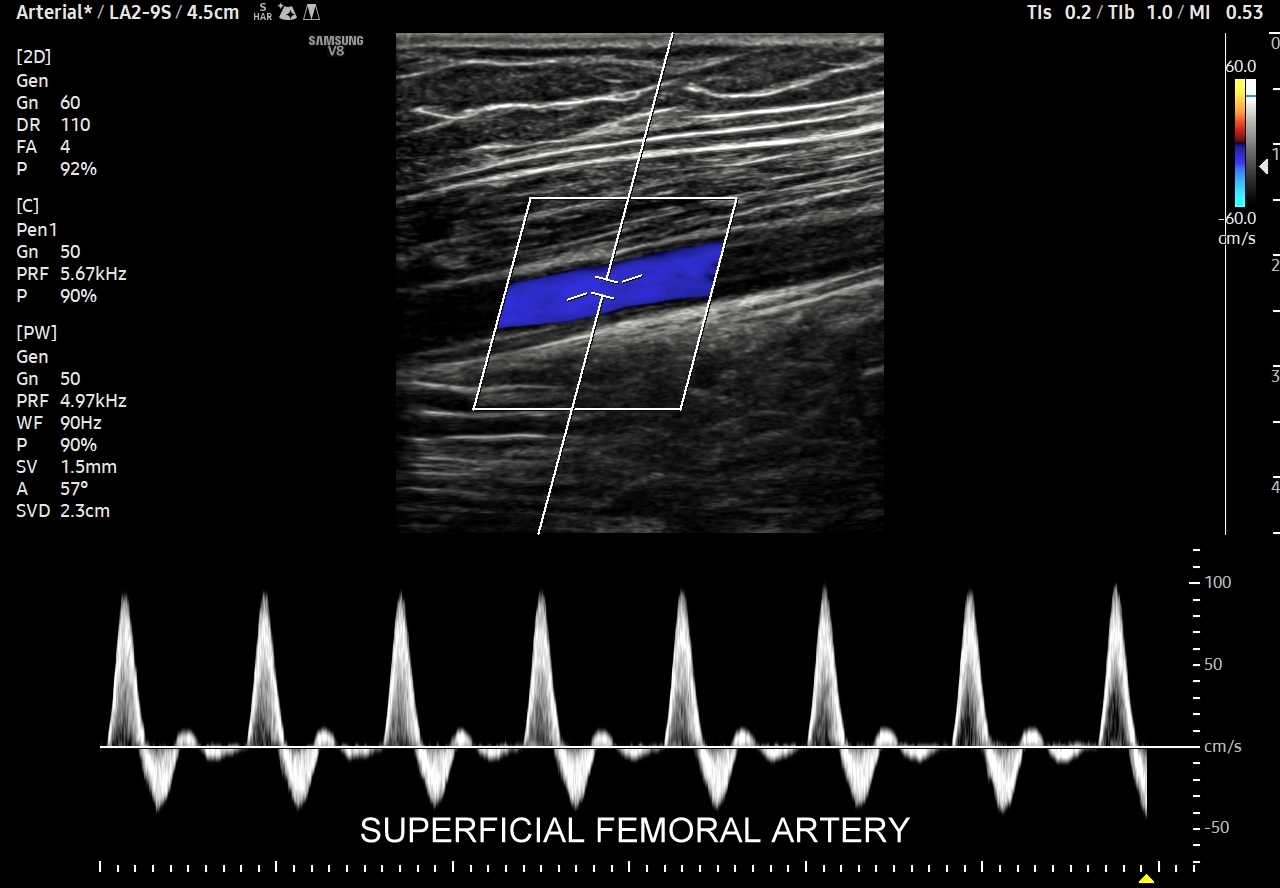

- Z kolei profile o wysokiej pulsacyjności charakteryzują się tym, iż posiadają wąskie i ostre piki skurczowe, a w fazie rozkurczowej odwrócone lub/i nieobecne przepływy. Profile tego typu występują w tętnicach unaczyniających kończyny.

W przypadku tętnic podążających do kończyn w warunkach spoczynkowych obserwuje się charakterystyczne wielozałamkowe profile przepływów zawierające od 2 do nawet 4 następujących po sobie przeciwstawnych załamków o zmniejszającej się amplitudzie, przy czym w tętnicach tych zwykle nie obserwuje się ciągłego przepływu w fazie rozkurczowej. Stały lub prawie stały przepływ rozkurczowy, tj. przepływ o pośredniej pulsacyjności, może pojawić się w tętnicach kończyn w trakcie intensywnego wysiłku fizycznego.

Podsumowując, przepływ krwi w konkretnych tętnicach, w tym jego przyspieszenie i prędkość, wynikają z 1/ charakteru pracy pompy, tj. serca; 2/ stanu naczyń per se, tj. elastyczności i drożności; oraz z 3/ właściwości biologicznych unaczynionego narządu. W związku z powyższym prawidłowy profil przepływu we wszystkich rodzajach tętnic w krążeniu dużym w warunkach fizjologicznych, tj. przy zdrowym sercu, zdrowych naczyniach i zdrowym docelowym narządzie, zawsze cechuje się szybkim narastaniem prędkości przepływu, czyli stromym ramieniem wstępującym; krótkim czasem akceleracji (ang. acceleration time) od początku tegoż ramienia do pierwszego załamania na nim, tj. zasadniczo nie przekracza 70 ms, a zwykle oscyluje wokół 30 ms. Poza tym w przypadku młodych i elastycznych tętnic podążających do kończyn, tj. naczyń z przepływem wysokooporowym, w fazie rozkurczowej przepływu obserwuje się wyższe załamki i często więcej załamków (zamiast jednego nawet do trzech). W krążeniu płucnym czas akceleracji prawidłowo przekracza 100 ms.